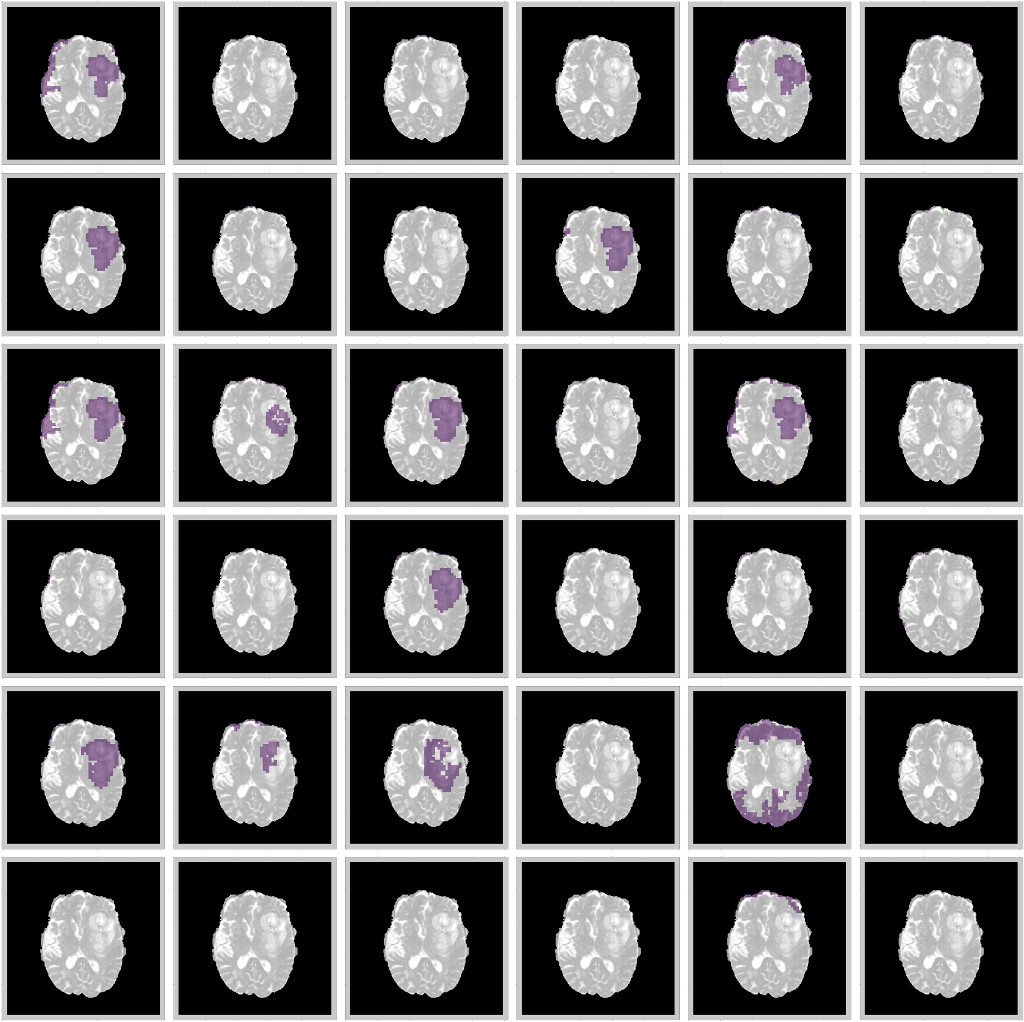

Where Φ(x|wt)Φconditional𝑥superscript𝑤𝑡\Phi(x|{w^{t}}) is the output of the neural network with weights wtsuperscript𝑤𝑡w^{t} on applying dropout on the tthsuperscript𝑡𝑡t^{th} iteration. The models are retrained with a dropout rate of 0.2 after each layer. At test time, a posterior distribution is generated by running the model for 100 epochs for each image. We take the mean of the posterior sampled distribution as our prediction and the channel mean of the variance from Equation 9 as the uncertainty (Kendall et al., 2015). The results of this are shown in Figure 7.

We find that regions which are misclassified are often associated with high uncertainty. For example, Figure 7a shows a region in the upper part of the tumor which is misclassified as necrotic tumor, but the model is also highly uncertain about this region. Similar behaviour is seen in Figure 7b. In some cases, the model misses the tumor region completely, but the uncertainty map still shows that the model has low confidence in this region (7d), while in some cases, boundary regions are misclassified with high uncertainty (7c). In a medical context, these are regions that radiologists should pay more attention to. This would encourage a sort of collaborative effort - tumors are initially segmented by deep learning models and the results are then fine-tuned by human experts who concentrate only on the low-confidence regions, Figure 1 shows.

Refer to caption

Figure 7: Uncertainty estimations (shown in red) for the DenseUnet using TTD for a selected set of images. Ground Truth(Left), Model Prediction(Middle), and Uncertainty(Right). Misclassified regions are often associated with high uncertainty.

9.4 Uncertainty

Figure 14: Uncertainty estimations (shown in red) for the DenseUnet (a,b,c,d) and ResUnet (e,f). Ground Truth(Left), Model Prediction(Middle), and Uncertainty(Right).